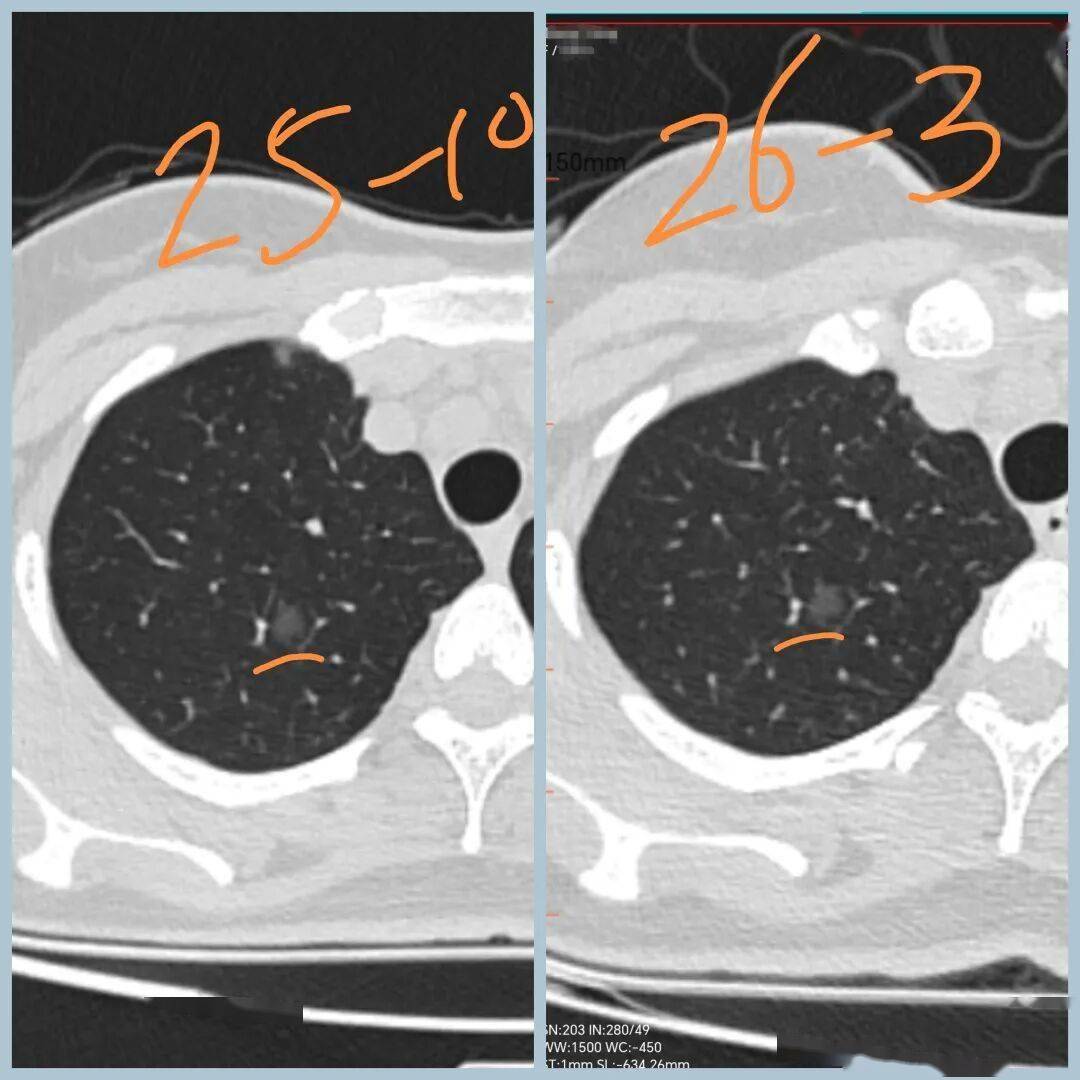

男性,40+岁,发现左下叶实性结节5年

后结节 逐渐增大

2026年3月CT示病变1.6cm

术前CT示:左肺下叶基底段实性结节,大小1.6cm,边界清,有浅分叶,内部密度不均,有点状高密度。看形态确实像良性。